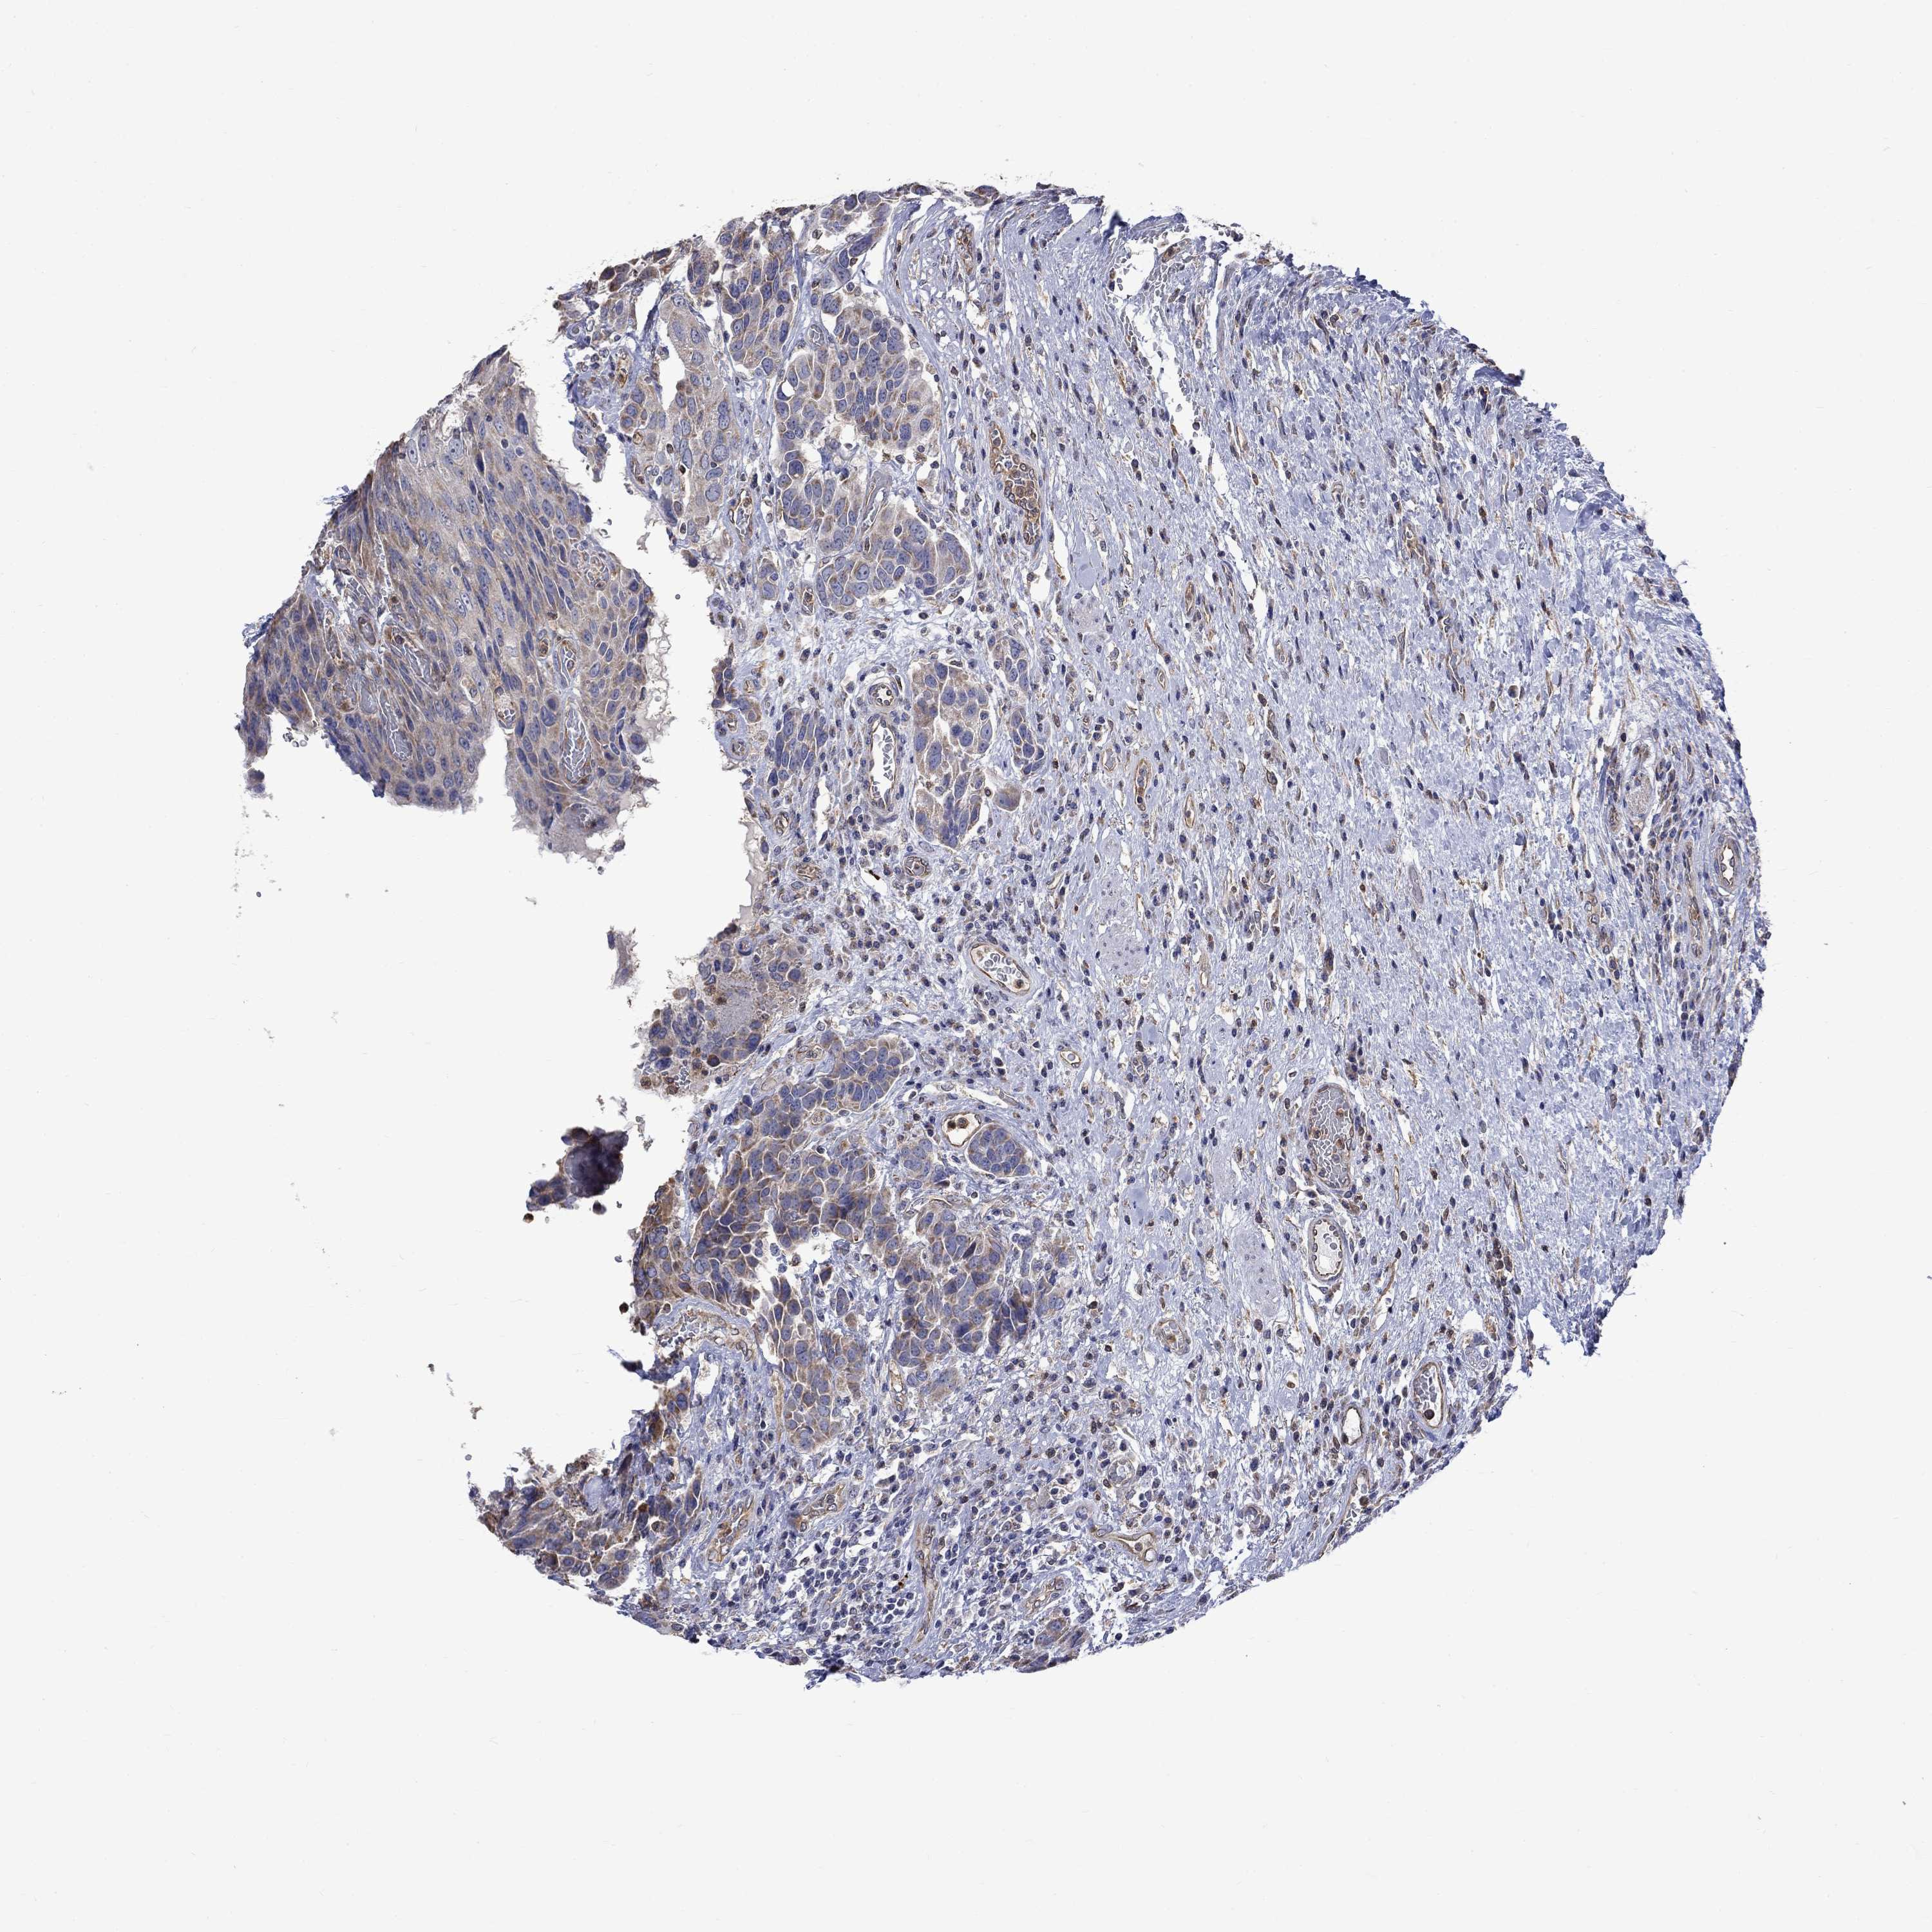

UROTHELIAL CANCER - Protein expressioni

A mouse-over function shows sample information and annotation data. Click on an image to view it in a full screen mode. Samples can be filtered based on level of antibody staining by selecting one or several of the following categories: high, medium, low and not detected. The assay and annotation is described here.

Note that samples used for immunohistochemistry by the Human Protein Atlas do not correspond to samples in the TCGA dataset.

Antibody stainingi

Antibody staining in the annotated cell types in the current human tissue is reported as not detected, low, medium, or high, based on conventional immunohistochemistry profiling in selected tissues. This score is based on the combination of the staining intensity and fraction of stained cells.

Each image is clickable and will lead to virtual microscopy that enables deeper exploration of all samples and also displays staining intensity scores, fraction scores and subcellular localization as well as patient and tissue information for each sample.

Antibody HPA017389

Antibody HPA063713

Staining

High

Medium

Low

Not detected

Intensity

Strong

Moderate

Weak

Negative

Quantity

>75%

75%-25%

<25%

None

Location

Nuclear

Cytoplasmic/membranous

Cytoplasmic/membranous,nuclear

Urothelial carcinoma, Low grade

Urothelial carcinoma, High grade

Urothelial carcinoma, NOS